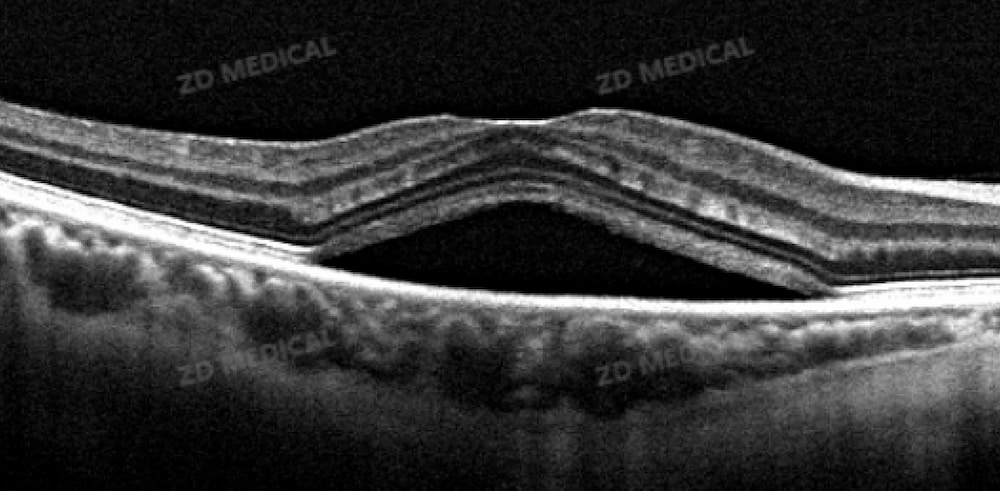

El fondo de ojo, como núcleo central de la transmisión de señales visuales, a menudo sirve como una "alerta temprana" de ceguera debido a sus lesiones microscópicas. Los métodos de examen tradicionales dificultan la captura de los cambios sutiles entre las capas de la retina. Sin embargo, la tecnología OCT ha logrado un gran avance gracias a su ventaja única de "biopsia óptica": mediante el principio de interferencia de luz coherente débil, puede reconstruir imágenes bidimensionales y tridimensionales del fondo de ojo con una profundidad milimétrica y una resolución micrométrica. Presenta con claridad marcadores clave de lesiones, como el derrame intrarretiniano (FIR) y el derrame subretiniano (FRS).

La tecnología central adoptada por ZD Medical OCT Puede realizar un escaneo retiniano completo en 3 segundos, con una resolución de imagen un 40 % superior a la de los equipos tradicionales. Incluso las diminutas protuberancias en la capa epitelial pigmentaria de la retina en pacientes con DMAE en fase inicial se pueden capturar con precisión. La función de lectura remota de película con IA+ integrada, junto con la revisión en línea por expertos en enfermedades de la retina, abarca todas las enfermedades oftálmicas. Esto fortalece eficazmente a las instituciones médicas primarias, supera las limitaciones de tiempo, espacio y recursos, estandariza los resultados diagnósticos, reduce la incidencia de diagnósticos erróneos y no diagnosticados, y minimiza al máximo los riesgos clínicos. Como se destaca en el "Consenso de expertos de 2025 sobre OCT en el fondo de ojo de China", la capacidad de la OCT para identificar lesiones tempranas supera con creces la de la fotografía de fondo de ojo en color tradicional, y la tasa de detección positiva es significativamente mayor, lo que permite ganar tiempo valioso para la prevención de la ceguera.